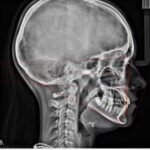

Digital & Manual Cephalometric

Easier, faster and precise diagnosis with digital Cephalometric using dolphin and FACAD Software's

3D Surgical Diagnosis and Planning

Comprehensive treatment planning of complex interdisciplinary cases using Dolphin Software